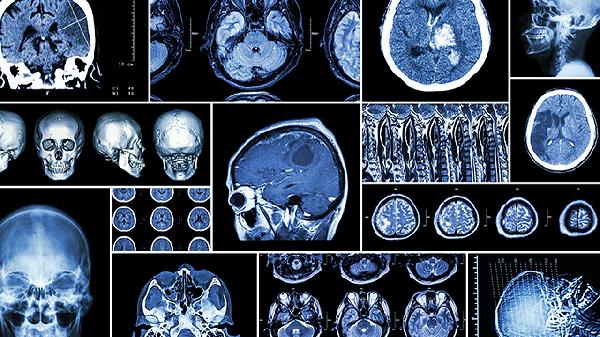

颅骨缺损直径超过3厘米是手术的主要指征之一。当缺损面积较小时,硬脑膜和头皮软组织可提供足够保护,此时手术必要性较低。但缺损直径超过3厘米时,脑组织失去骨性支撑,易受外力损伤,可能引发脑组织移位、脑脊液循环障碍等问题。此时需通过钛网或聚醚醚酮材料进行修补,恢复颅腔完整性。缺损部位若位于额部等显露区域,即使面积较小,但严重影响外观时也可考虑手术修复。患者需完成头颅CT三维重建检查,精确测量缺损范围,评估周边骨质条件。手术时机一般选择在去骨瓣术后3-6个月,待头皮瘢痕软化、颅内压稳定后进行。